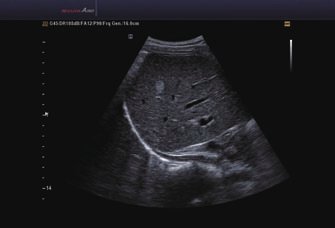

Das Samsung Accuvix A30 ist ein hochwertiges Ultraschallsystem, das mit seiner 3D-Technologie herausragende Ergebnisse ermöglicht. Das Sonographiegerät besitzt 5 Sondenanschlüsse und ist mit 20 unterschiedlichen Schallköpfen kompatibel. Mit dem A30 können Schallköpfe vom Typ Konvex, Mikrokonvex, 3D-Konvex, CW, Phased Array, Linear und Endokavitär verwendet werden. Bei zwei der Sonden handelt es sich um S-VUE Ultraschallsonden, die durch ihre höhere Bandbreite noch feinere Scans erzeugen.

• 2D-Modus

• M-Modus